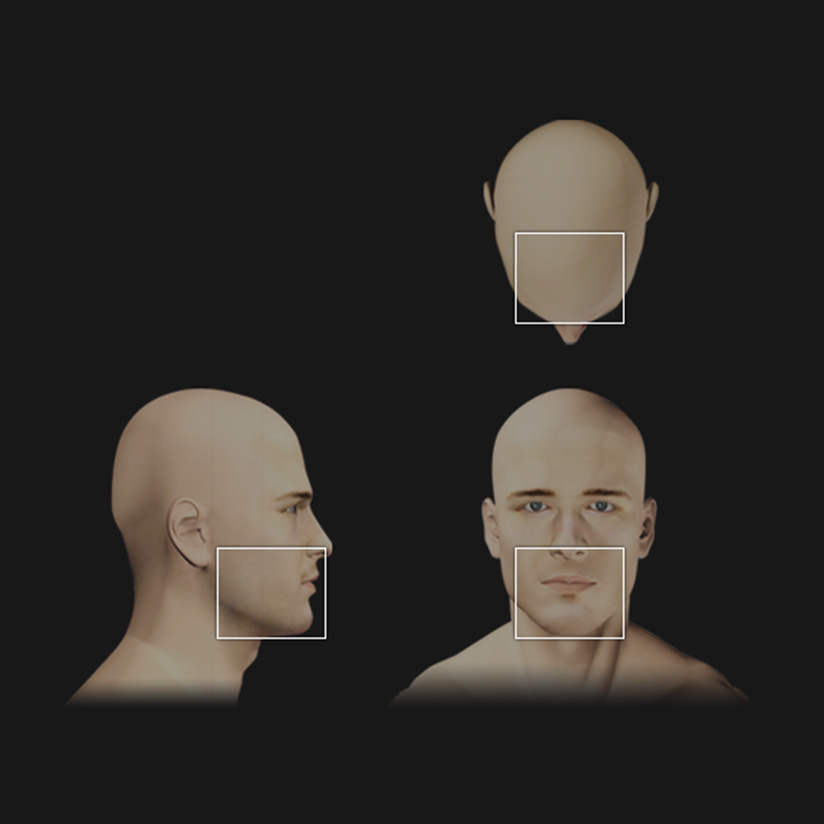

Snimak 12×9 cm, najćešće se prostire do angulusa mandibule i infraorbitalnog foramena

- Višestruki prikazi: 3D render, multiplanar view, cross-section